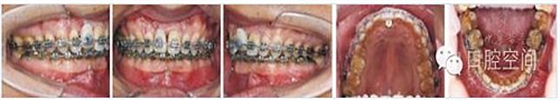

36歲男性患者,因前牙咬合過深影響上前牙種植修復,尋求正畸治療改善咬合關(guān)系。直絲弓矯治器固定矯治半年后,雙側(cè)前磨牙鎖頜解除,下牙列排齊,更換至0.017英寸×0.025英寸鎳鈦絲。在下頜中切牙間前庭溝處,局麻下切開黏膜,正中聯(lián)合部位植入一枚微螺釘(1.6 mm×9 mm,慈北醫(yī)療器械有限公司)。通過直徑0.30 mm結(jié)扎絲連接微螺釘頭部,形成牽引鉤形狀,以微螺釘種植體支抗行閉合式牽引壓低下頜切牙。8個月后前牙覆頜正常。固定矯治19個月,右上中切牙種植修復完成,去除固定矯治器,進入保持階段?;颊呙骖M像及X線片見圖10,圖11,圖12,圖13,圖14,治療前后頭影測量結(jié)果見表3。

圖11病例2治療中像,以微螺釘支抗閉合式牽引壓低切牙改善深覆